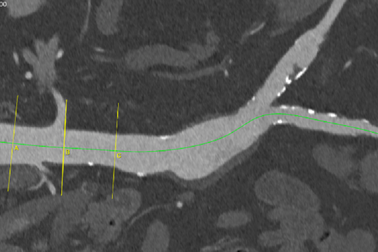

Phối hợp liên viện cứu cụ ông bị phình bóc tách động mạch chủĐến bệnh viện thăm khám sau những cơn đau bất thường, cụ ông 75 tuổi được bác sĩ chẩn đoán bị phình bóc tách động mạch chủ bụng chậu. Trên nền bệnh khí phế thủng gây mê, nguy cơ tử vong cao, các bác sĩ quyết định đặt Stent Graft giúp bệnh nhân thoát khỏi nguy hiểm.